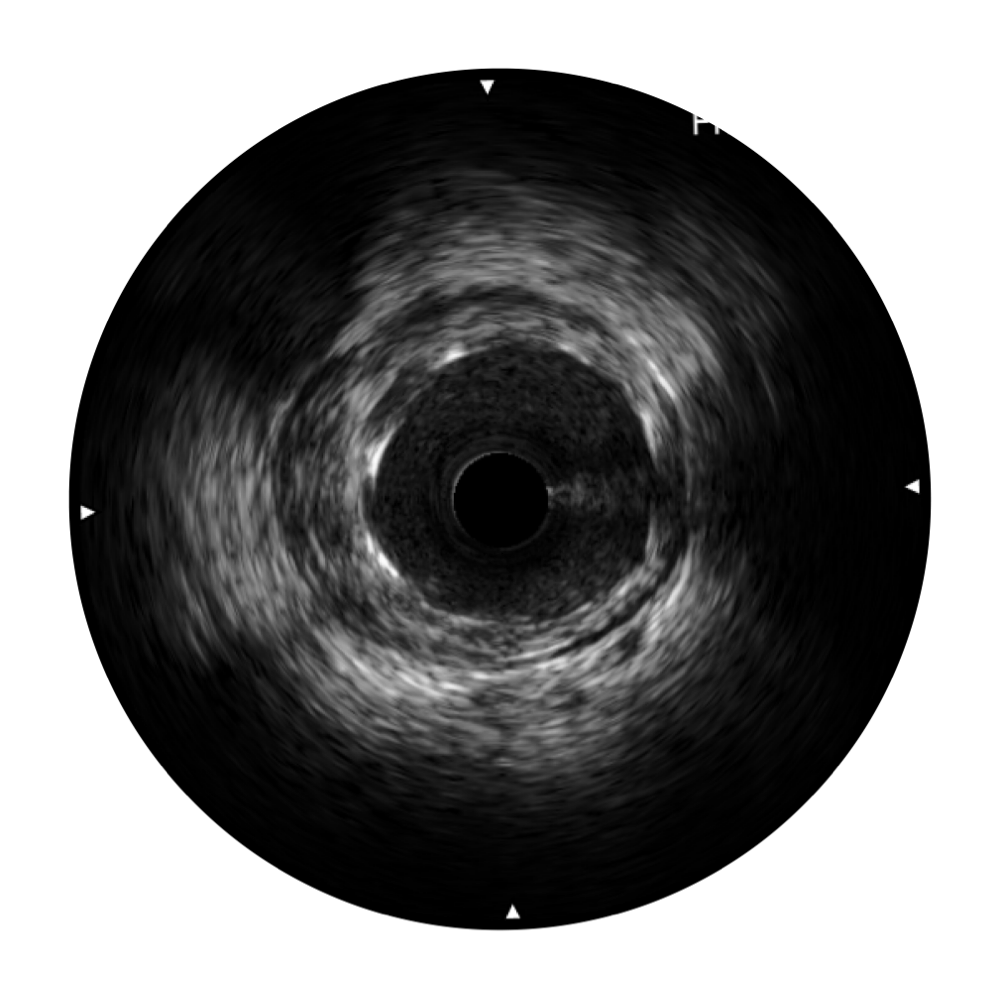

临床图

远场分支血管及导丝

支架内血栓

组织脱垂